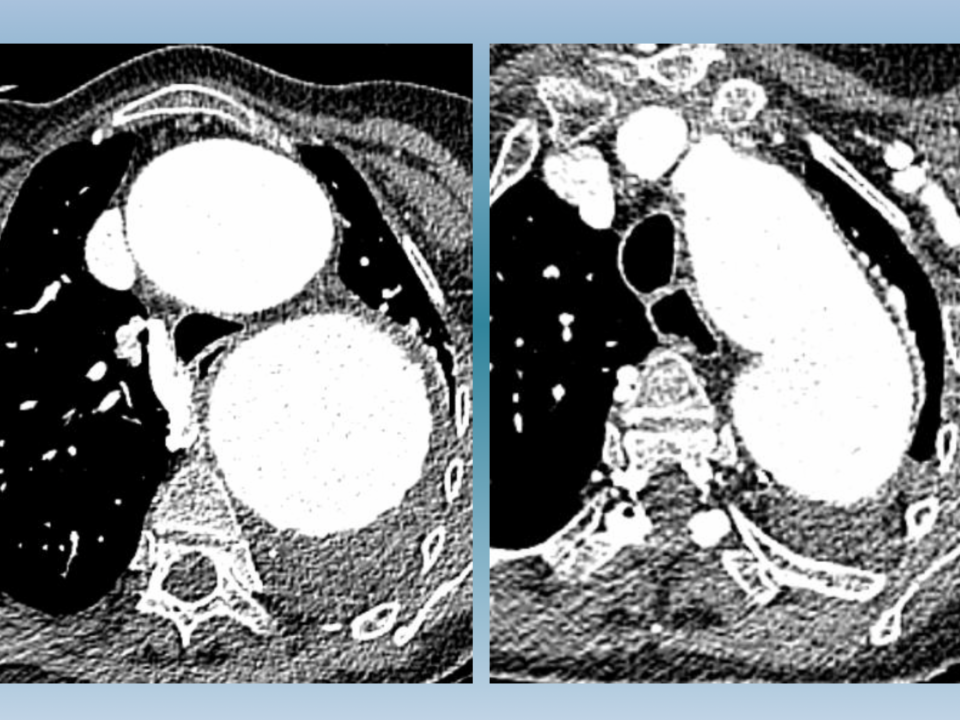

Ce cas clinique met en lumière l’aggravation progressive d’une difficulté respiratoire chez un patient fragilisé par des infections respiratoires chroniques, un état de faiblesse générale et la présence d’un important […]Reprise des Réunions de l’Association des Pneumologues de la Côte d’Azur (A.P.L.C.A.)